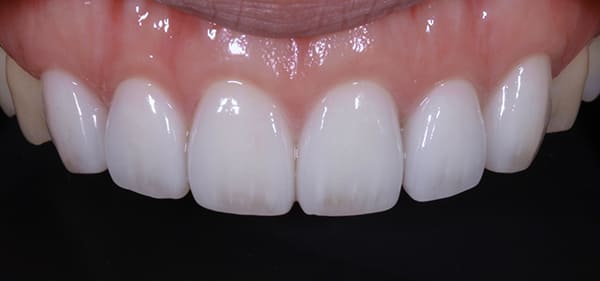

ワックスアップ

最終的な被せ物(補綴物)の仕上がりをイメージするために、事前にワックスアップ(模型上でのシミュレーション)を行いました。

これにより、歯の長さや形、スマイル時の見え方などを確認し、理想的な仕上がりを患者さまと共有することができます。

またこのワックスアップは、手術時に歯ぐきの位置や形を正確に整えるためのガイド(ステント)としても活用します。